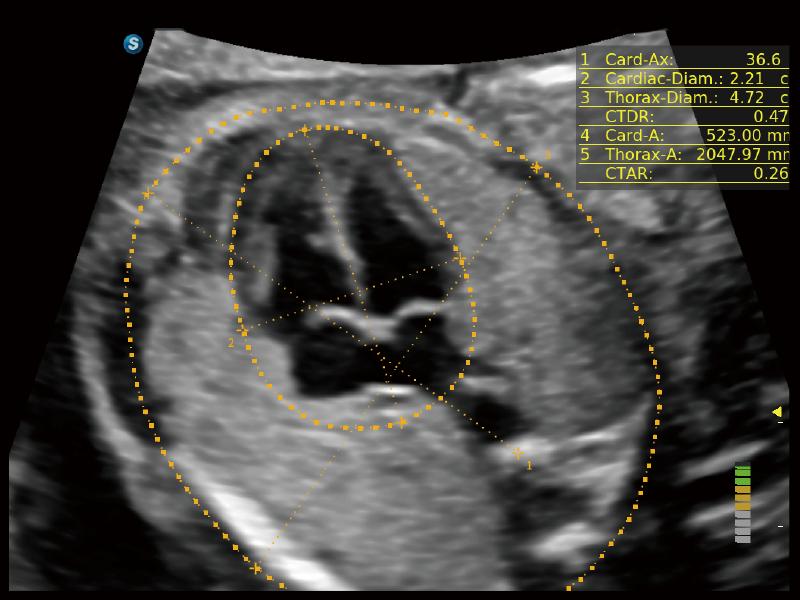

作為開(kāi)立醫(yī)療全新打造的超高端旗艦超聲產(chǎn)品,從探頭抬起喚醒開(kāi)啟掃查到多維探頭發(fā)射接收,通過(guò)先進(jìn)的場(chǎng)成像發(fā)射、自適應(yīng)聚合重建等技術(shù),基于RF Data原始射頻數(shù)據(jù)在圖像生成、高端功能等方面實(shí)現(xiàn)突破,為婦產(chǎn)科、兒科提供全方位臨床解決方案。

夢(mèng)溪?P80以“關(guān)愛(ài)女性”為基石,提供全方位的解決方案,量身定制以滿(mǎn)足女性的健康需求,涵蓋婦科、生殖健康檢查、產(chǎn)前篩查及產(chǎn)后康復(fù)等領(lǐng)域。